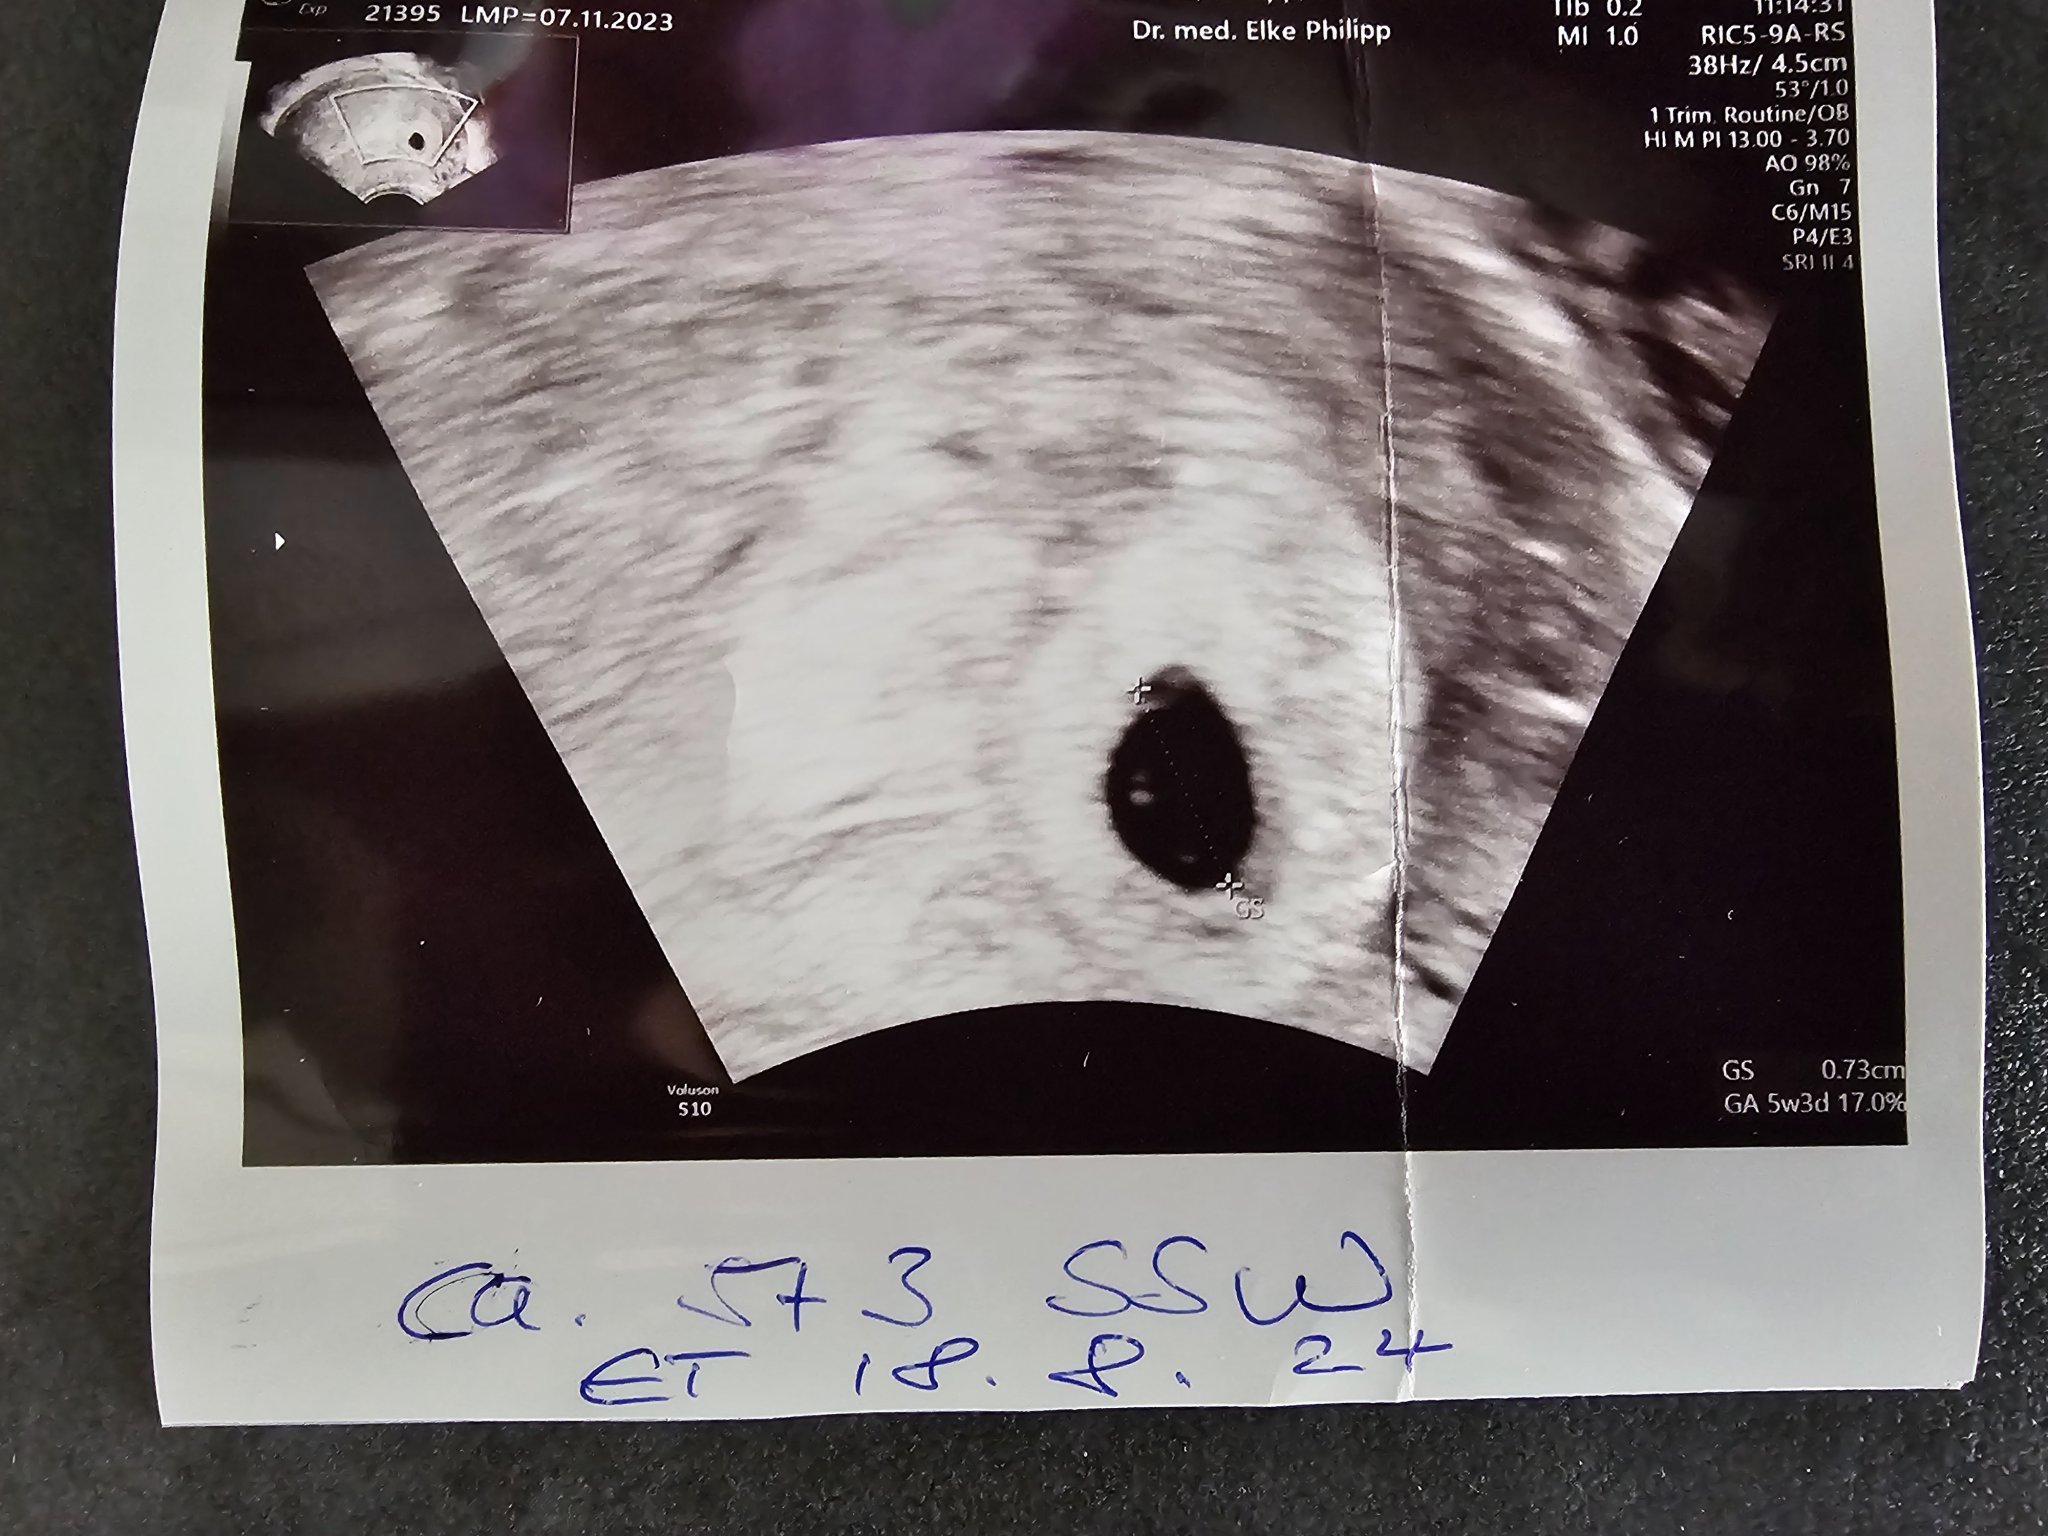

Кога е подходящо да се направи първият преглед при бременност?

Какви са някои препоръки за първия преглед по време на бременност?